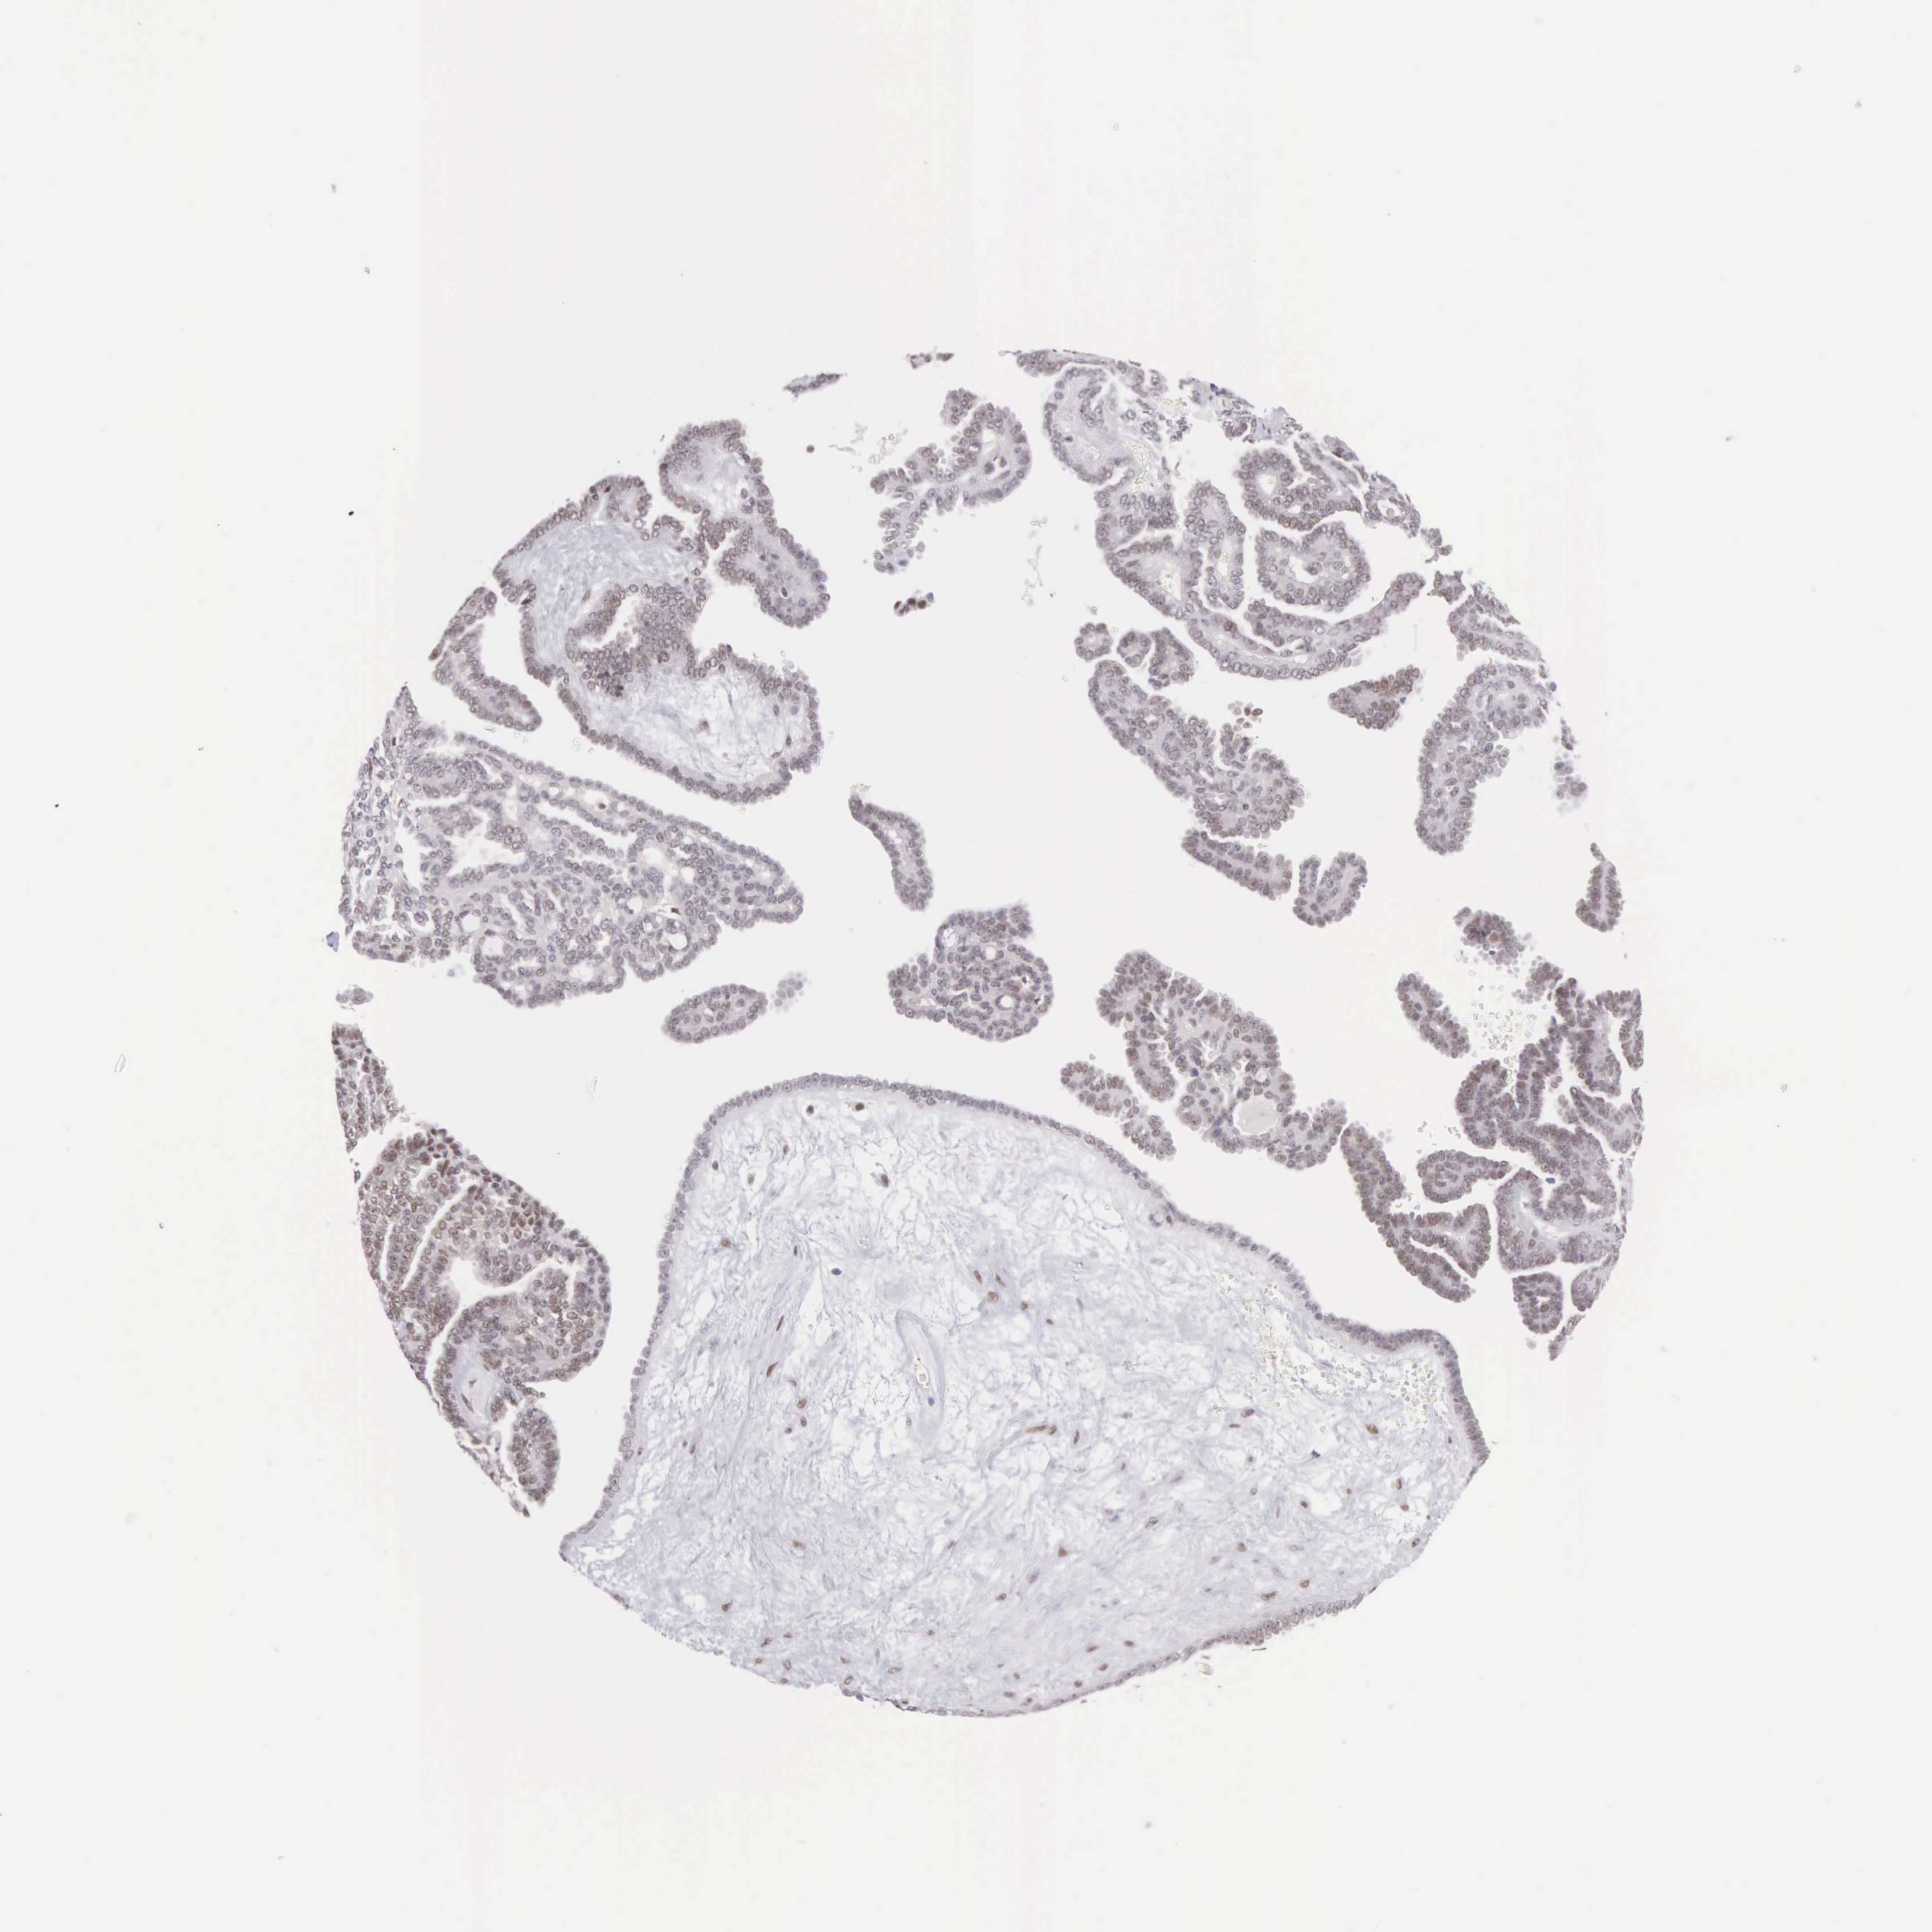

OVARIAN CANCER - Protein expressioni

A mouse-over function shows sample information and annotation data. Click on an image to view it in a full screen mode. Samples can be filtered based on level of antibody staining by selecting one or several of the following categories: high, medium, low and not detected. The assay and annotation is described here.

Note that samples used for immunohistochemistry by the Human Protein Atlas do not correspond to samples in the TCGA dataset.

Antibody stainingi

Antibody staining in the annotated cell types in the current human tissue is reported as not detected, low, medium, or high, based on conventional immunohistochemistry profiling in selected tissues. This score is based on the combination of the staining intensity and fraction of stained cells.

Each image is clickable and will lead to virtual microscopy that enables deeper exploration of all samples and also displays staining intensity scores, fraction scores and subcellular localization as well as patient and tissue information for each sample.

Antibody HPA000826

Staining

High

Medium

Low

Not detected

Intensity

Strong

Moderate

Weak

Negative

Quantity

>75%

75%-25%

<25%

None

Location

Nuclear

Cytoplasmic/membranous

Cytoplasmic/membranous,nuclear

Cystadenocarcinoma, mucinous, NOS

Carcinoma, endometroid

Cystadenocarcinoma, serous, NOS